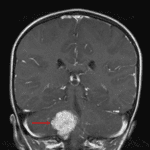

Indication: Headache, imbalance

- Avidly enhancing extra-axial mass with frondlike projections measuring 3.5 x 3 x 3 cm centered in the right foramen of Luschka with superior extension into the fourth ventricle and inferior extension through the foramen magnum

- Corresponding T2 signal hyperintensity

- Numerous foci of internal susceptibility artifact

- Corresponding mass effect on the adjacent cerebellum and brainstem without parenchymal edema

- No hydrocephalus

Choroid plexus papilloma